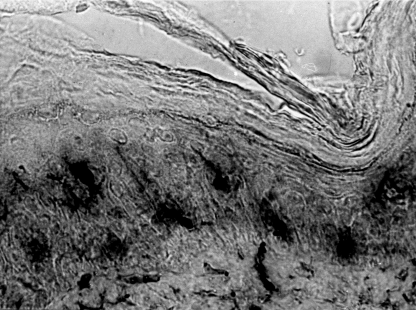

- Кошевенко Ю. Н. первым из отечественных дерматологов в 1983 году стал изучать в коже клетки Лангерганса (тканевые макрофаги), очень важный элемент тканевого иммунитета. И доказал их важнейшую роль в патогенезе витилиго!

- Кошевенко Ю. Н. впервые в мире делал это сразу в двух проекциях (вертикальной и горизонтальной) по разработанной самим же комбинированной методике (рац.предложение № 36):

Подобные исследования в стране больше никогда и никем не проводились.